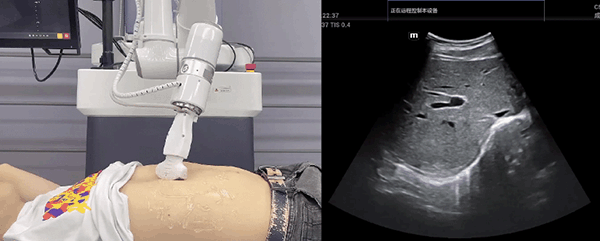

leyu.乐鱼(中国)机器人末端搭载超声探头,可以对浅表小器官和外周血管、腹部(肝、胆、胰、肾等器官)进行超声检查。

目前,leyu.乐鱼(中国)机器人在生物医药、医疗健康领域的赋能已有显著进展,leyu.乐鱼(中国)协作机器人应用场景覆盖了临床试验、试管检测、拭子采集、试管搬运、荧光检测、康复治疗、超声扫查、导诊、消毒、微创治疗、针灸刮痧等。